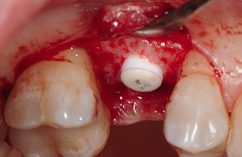

Unter Lokalanästhesie erfolgte nach krestaler Schnittführung die Aufklappung (Abb. 5) und die Aufbereitung des Implantatbettes gemäß dem chirurgischen Protokoll für NobelPearl mit den Bohrern des NobelPearl Surgical Tray. Nach Ankörnung mit dem Rosenbohrer wurde unter Beachtung der korrekten Implantatachse die 1. Bohrung mit dem zylindrischen Pilotbohrer Ø 2,3 mm auf die geplante Länge von 10 mm angelegt. Für die unterschiedlichen Längen stehen in der Folge formkongruente Profilbohrer zu Verfügung. So wird für die weitere Aufbereitung zunächst der Profilbohrer „small“, Länge 10 mm, Ø 3,3 mm (Farbcodierung violett), und danach der Profilbohrer „regular“, Länge 10 mm, Ø 4,2 mm (Farbcodierung gelb, hier mit Tiefenstopp), ausgewählt (Abb. 6).Da das NobelPearl-Implantat nicht selbstschneidend ist und beim Eindrehen des Implantats der Werkstoff Keramik keine Temperatur wie ein Titanimplantat ableitet, muss als letztes Instrument der Gewindeschneider auf die gesamte Implantatlänge eingesetzt werden.

Die Implantate wurden im Anschluss mit einer ausreichenden Primärstabilität von 30 Ncm und einem suprakrestalen Anteil 0,6 mm platziert. Diese suprakrestale Positionierung wird durch einen gegebenenfalls am Profilbohrer anbringbaren Tiefenstopp (Abb. 7) vereinfacht. Für das Einbringen der Implantate steht ein neues, zur „Inter-X“-Innenverbindung formschlüssiges Eindrehinstrument (Abb. 8) zu Verfügung, wodurch eine optimale Kraftübertragung während des Inserierens des Implantats gewährleistet wird (Abb. 9). Die Einheilkappen sind deutlich abgeflacht und ermöglichen einen einfachen primären Wundverschluss (Abb. 10 und 11). Im vorliegenden Fall verlief die Wundheilung komplikationslos. Nach einer auch für Keramikimplantate heute üblichen Einheilungszeit von 3 Monaten zeigten sich die Implantate in der Röntgenkontrollaufnahme stabil osseointegriert (Abb. 12). Es fanden sich an beiden Implantat-Loci entzündungsfreie Weichgewebsverhältnisse, woraufhin mit der prothetischen Versorgung des Implantats begonnen werden konnte.